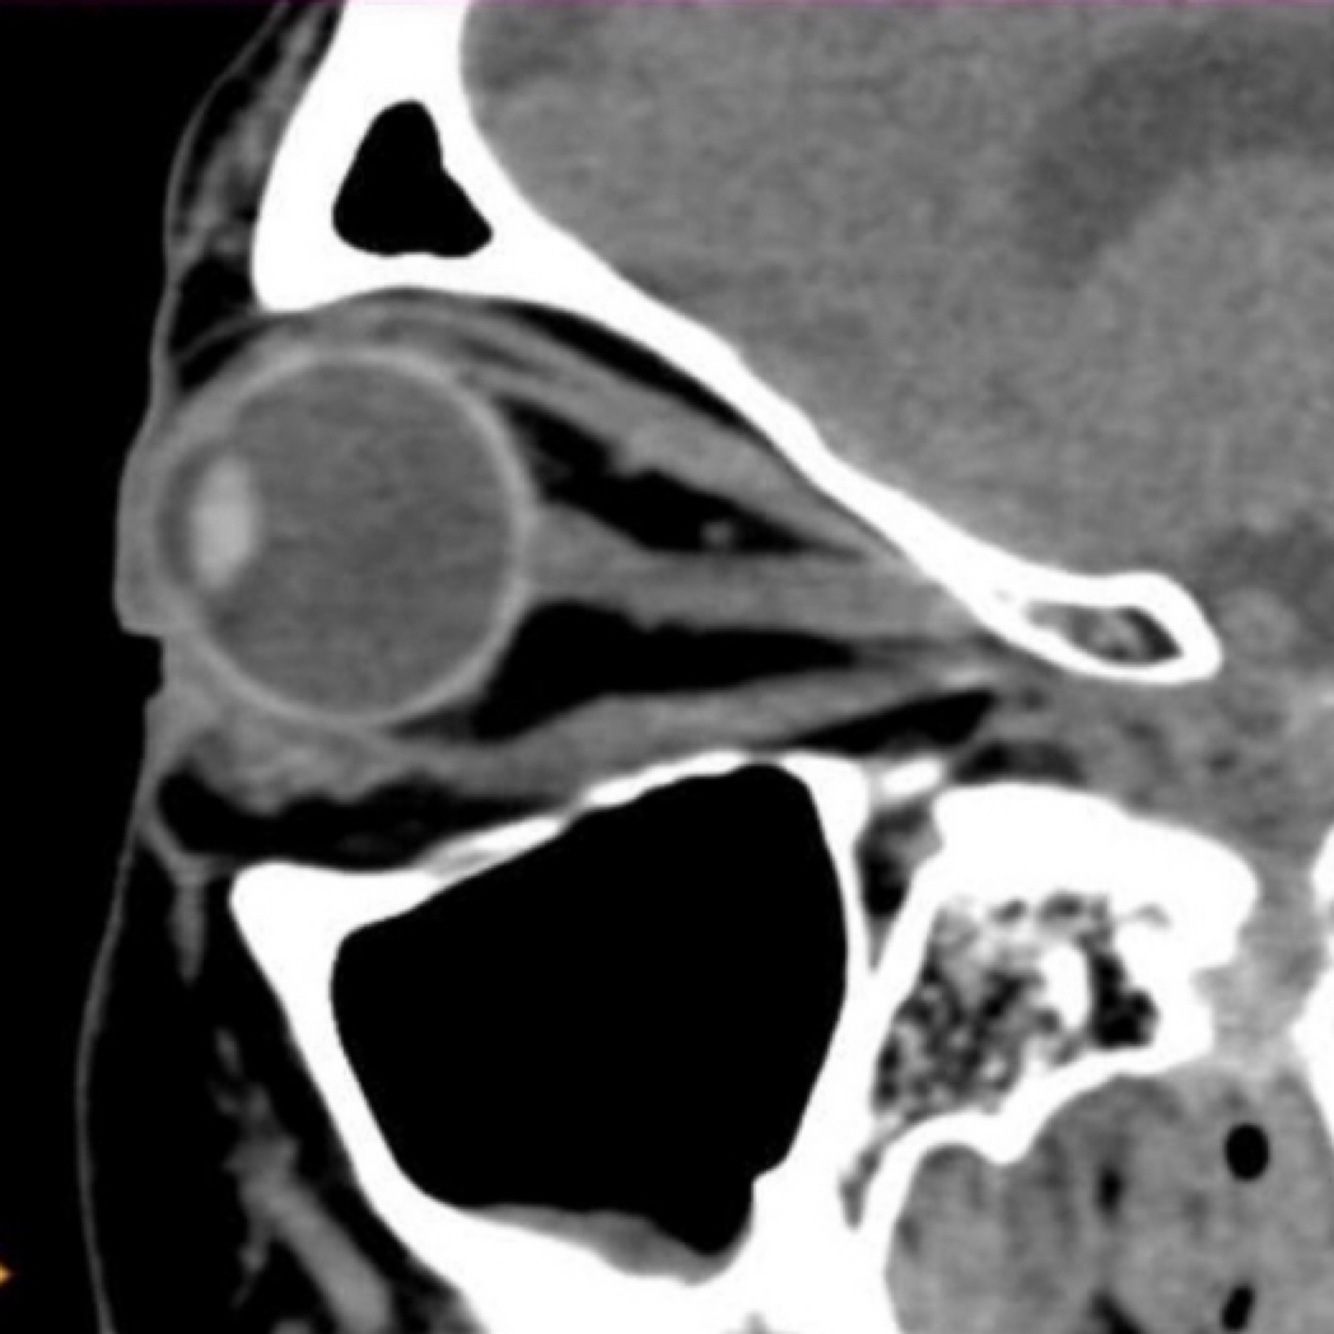

Cual es la anatomía del ojo?

• Es el sentido mas utilizado

• Es el órgano principal del sistema visual, formado por el globo ocular y los anexos

• Es una esfera de 25 mm de diámetro y pesa 8 grs aprox. Se encuentra ubicado en la cavidad orbitaria

Nombra las estructuras anatómicas referentes al ojo

1. Cuerpo ciliares

2. Lente

3. Iris

4. Pupila

5. Córnea

6. Humor acuoso

7. Ligamento de suspensión de la lente

8. N. Óptico

9. Punto ciego

10. Vasos sanguíneos

11. Fovea

12. Retina

13. Corridos

14. Esclerotica

How well did you know this?